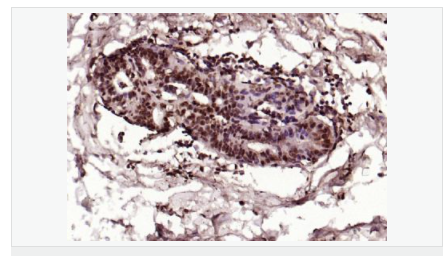

產品應用ELISA=1:5000-10000 IHC-P=1:100-500 IHC-F=1:100-500 Flow-Cyt=1μg/Test ICC=1:100 IF=1:100-500 (石蠟切片需做抗原修復)

image.png